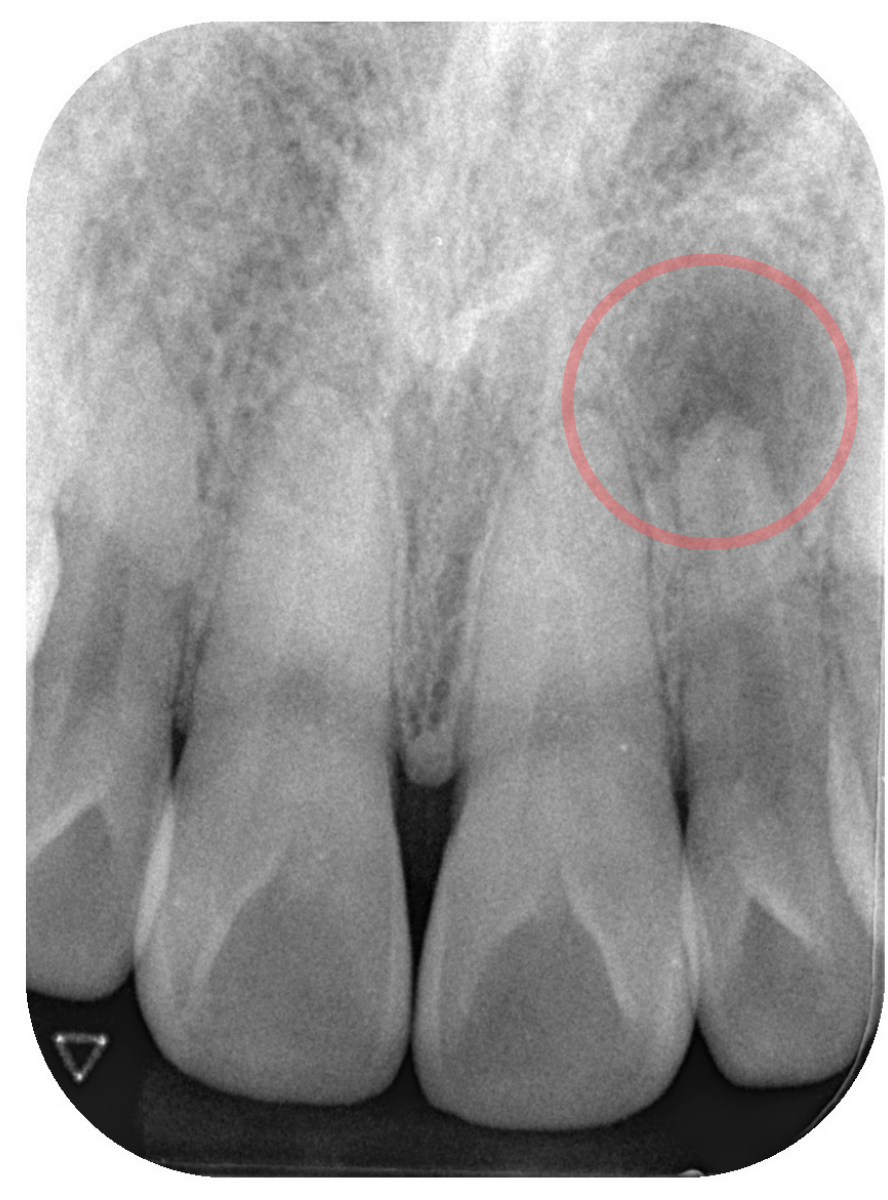

レントゲン撮影で歯の内部を確認します。

すると、前歯の根尖(根っこの先)に黒い影(炎症)があります。

これは、歯の神経が死んでしまっている証拠です。